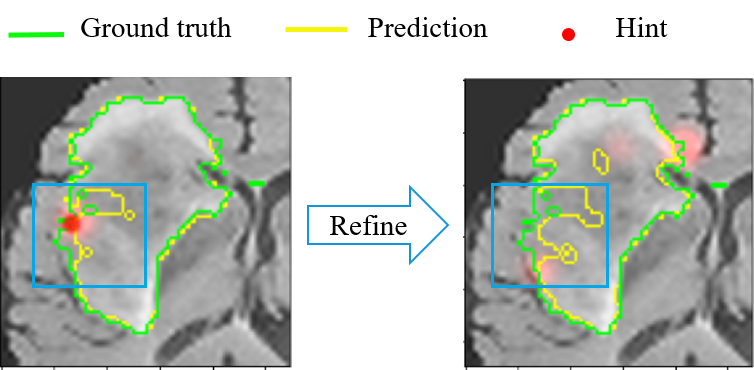

Refer to caption

(a) Correction information is ignored

(b) Refined result becomes worse

Figure 2: Segmentation refining failure after long-term interactions on BraTS2015 images: a) The segmentation model can not fully understand the hint information or just ignores it. b) The interactive segmentation model could misunderstand the expert’s interaction correction, which results in the worse result;

Methods such as BIFSeg Wang et al. (2018a) and DeepIGeos Wang et al. (2018b) model user interactions as hard constraints through conditional random fields (CRFs) end-to-end training. However, these model more focus on the one-step interaction and the refined segmentation after the first step cannot be efficiently used in these model Liao et al. (2020); Ma et al. (2020). Thus, these model can not utilize the long-term interactive information but the short-term interactive information efficiently. The follow-up InterCNN Bredell et al. (2018) and other methods Liao et al. (2020); Ma et al. (2020) are improved on DeepIGeos and BIFSeg, modeling the problem as an iterative interaction problem, which are more focus on the multi-step interaction. Therefore, these method can cover the data distribution corresponding to different interaction levels in the training phase to effectively use long-term interactions, while ignoring the stochasticity or uncertainty of the model makes it difficult for them to effectively use short-term interactive information. Existing interactive methods cannot effectively utilize both short-term and long-term interactive information at the same time, which leads to the interactive misunderstanding phenomenon***This phenomenon will be discussed in detail in the Section 3.3.. Figure 2 presents this phenomenon when implementing the popular interactive segmentation algorithm InterCNN Bredell et al. (2018) on the BraTS2015 dataset. The algorithm ignores the expert’s correction information as in Figure 2(a), and even be adversely affected by correction information as in Figure 2(b). These inconsistencies between hint information and the refined results indicate that existing algorithms still face the critical challenge of inefficiency utilization of interactive correction information. The reason for segmentation refining failure is that, at the end of the interactive procedure, the total loss of the model will guarantee the main area’s priority and ignore some small but challenging areas, such as edges. The regions that are insensitive to interactive correction information could be considered hard-to-segment regions Nie et al. (2019); Shrivastava et al. (2016), which leads to mediocre segmentation refinement. If these regions are not paid more attention during the training stage, the segmentation model will inevitably dominate those easy-to-segment regions. This problem is more serious for medical images, where the hard-to-segment regions usually are tumor boundaries and are very important for clinical diagnosis and surgery. Therefore, it becomes urgent to improve the utilization of correction information, especially for the hard-to-segment regions.